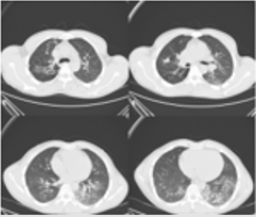

His laboratory exams showed; pH 7.22, lactate 3.2 mmol/L, hematocrit 47%, hemoglobin 14.8g/dL, white blood cells 17300/ μL (neutrophils 14600/μL), platelets 292000/μL, aspartate aminotransferase 5463U/L, alanine aminotransferase 4406 U/L, lactate dehydrogenase 837 U/L, creatine kinase 1.504 U/L, troponin-I 1951 pg/mL, creatinine 2.11mg/dL, urea 80 mg/ dL, procalcitonin 4,6 ng/mL, ferritin 2379ng/mL, International Normalized Ratio (INR) 1.3, C-reactive protein 12 mg/L. Acute pathology was not observed in brain computed tomography (CT) and diffusion magnetic resonance imaging (MRI) images taken for the patient’s neurological complaints (Figure 1). In thorax CT imaging, In the bilateral lung parenchyma, ground-glass is as with band formations were observed. There was a conversion to mild consolidation, which shows a tendency to merge in the ground glass areas of the left lung lower lobe basal. Low-density nodules accompanied by traction bronchiectasis with calcification in the right upper lobe posterior and upper lobe anterior and sequel changes (viral pneumonia + sequelae change) were observed (Figure 2). There was no major pathology in urinary and hepatobiliary ultrasonography evaluations due to an increase in liver and kidney function parameters. Although the patient had no acute electrocardiogram findings, a cardiology consultation was planned due to the high troponin present. Cardiac evaluation of the patient was performed with echocardiography and it was thought that the current height was secondary to the systemic state. Due to its neurological findings; Despite the absence of acute imaging pathology, the neurological evaluation was requested, and the patient was evaluated to have no acute neurological etiology because of the neurology consultation.